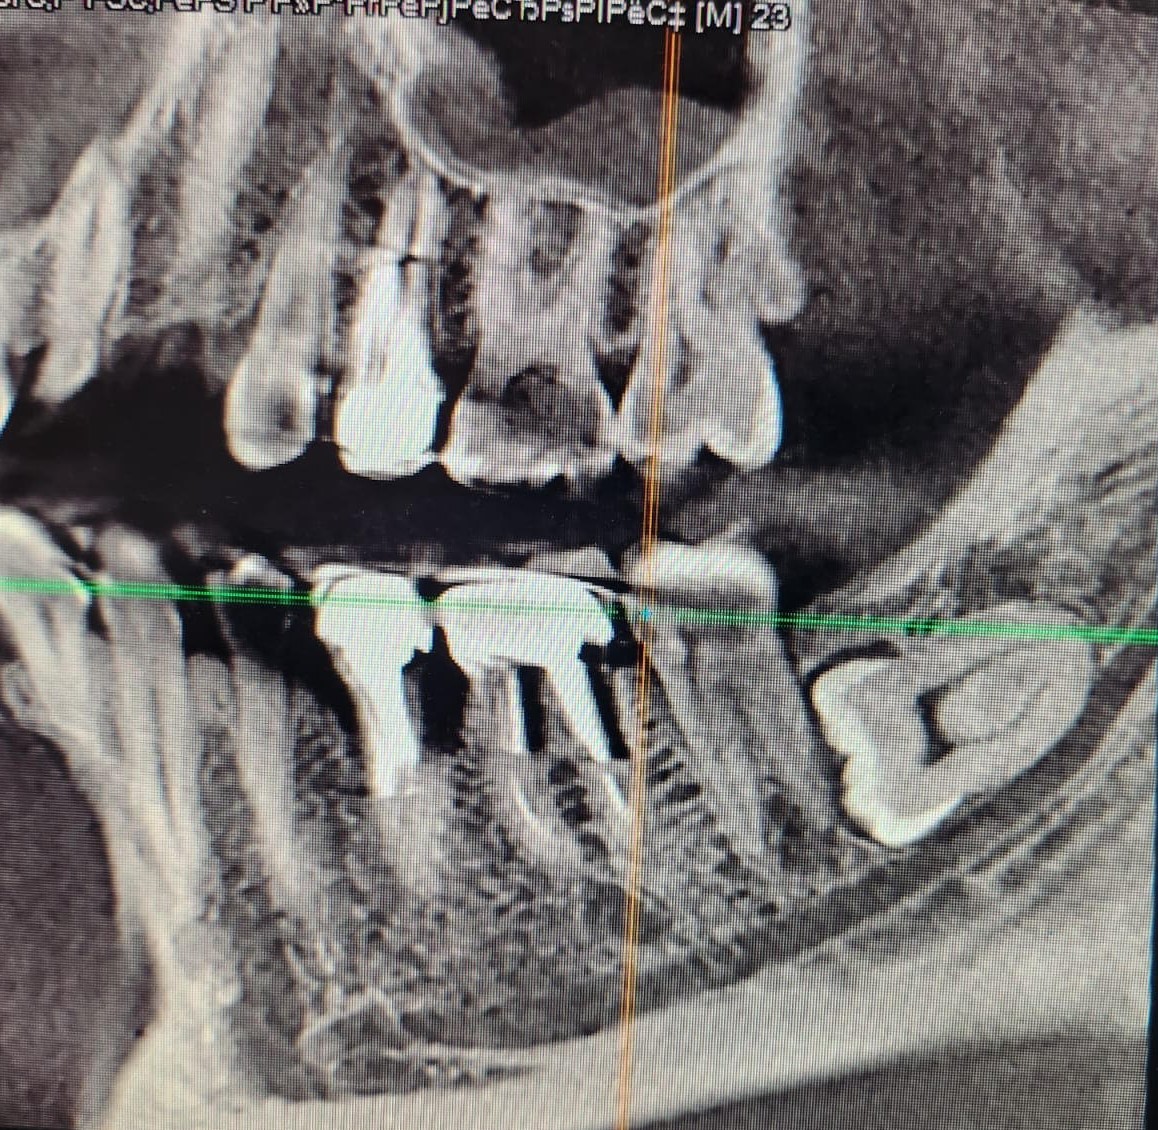

Горизонтальный – зуб мудрости, черная полоска под ним – нижнечелюстной нерв.

Открываю я снимок и вижу, что действительно так и было:

Черная полоска, уходящая в правый нижний угол картинки, отмеченная кружком, и есть то место, где был перебит нерв.